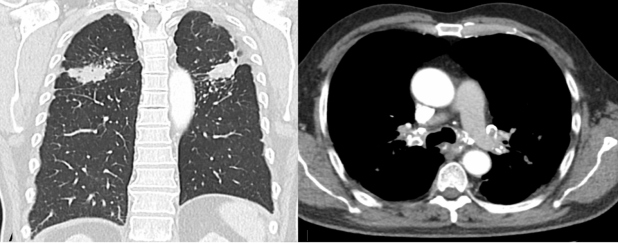

Paciente masculino de 68 años de edad con diagnóstico de adenocarcinoma de recto con mutación KRAS, estadio IV por metástasis hepáticas, con antecedentes de tabaquismo y exposición laboral crónica al granito, sin elementos de protección personal. Entre los estudios de extensión iniciales, se realizó tomografía computarizada (CT) de tórax encontrándose ganglios mediastinales con calcificaciones en “cáscara de huevo”, nódulos aleatorios que confluyen en segmentos posteriores de los lóbulos superiores asociados a masas simétricas con densidad de tejido blando y nodularidad subpleural, todos hallazgos relacionados con silicosis conglomerada (Fig. 1). Recibió tratamiento con 6 ciclos de quimioterapia esquema BEVACIZUMAB + FOLFOX6 con respuesta completa tanto del tumor rectal primario como de las metástasis hepáticas.